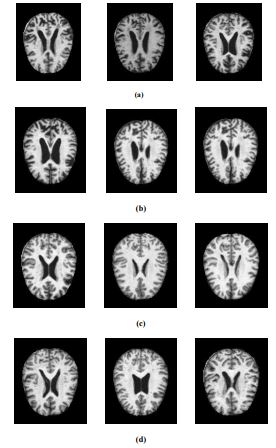

For this experiment, the Alzheimer's dataset [1] obtained from Kaggle is used. It is the combination of Alzheimer's Disease Neuroimaging Initiative (ADNI) dataset and the Open Access Series of Imaging Studies (OASIS) dataset. The data has four classes of images, both in training as well as testing sets, as mild dementia, moderate dementia, non-dementia, and very mild dementia. This dataset consists of a cross-sectional collection of 6488 different subjects aged between 18 and 96 with 3 or 4 individuals per subject. Also, this dataset contains 46.7% and 53.3% as women and men subjects, respectively. The training and validation dataset consists of about 5,121 MRI images of sizes 224, 224, and 3. The pre-processed images are augmented by rotating, zooming, horizontal flip, and vertical flip [15]. The data collected includes mild dementia-717, moderate dementia-52, non-dementia-2560, and very-mild dementia-1792. The test dataset consists of 1,367 MRI images, including mild dementia-167, moderate dementia-12, non-dementia-640, and very-mild dementia-548. The MRI images of the various Alzheimer’s stage affected are extracted from the dataset and are illustrated in Fig. (2).